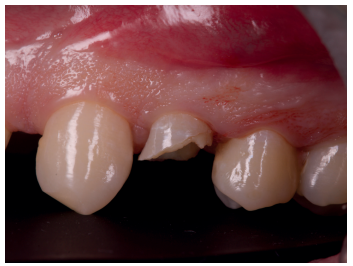

Se presenta en el Máster en Cirugía Oral, Implantología y Periodoncia de la Universidad Alfonso X El Sabio (Madrid, España) un paciente de 24 años derivado para exodoncia del primer premolar superior izquierdo y colocación inmediata de implante debido a una fractura corono-radicular como consecuencia de caries asintomática, con margen distal 2 mm subgingival y limitada estructura remanente (Figuras 1 y 2). Después de un estudio completo del caso, en colaboración con el Máster en Endodoncia de la misma facultad, se planificó la realización de la extrusión quirúrgica, endodoncia y posterior rehabilitación del diente. Dentro de este estudio resultaron de vital importancia las pruebas radiológicas, compuestas por radiografías periapicales y CBCT, que confirmaron la compatibilidad de la anatomía radicular con la realización de una extrusión mínimamente traumática.

con fractura corono-radicular.

fractura corono-radicular.